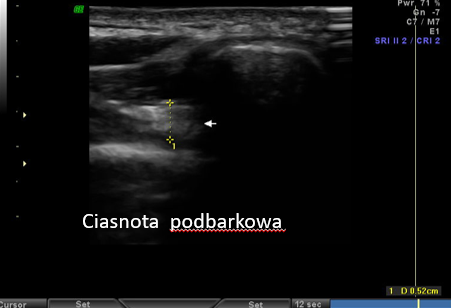

3. Zespół ciasnoty podbarkowej (impingement)

To schorzenie polegające na konflikcie struktur w obrębie barku podczas ruchu.

USG umożliwia:

- ocenę przestrzeni podbarkowej

- obserwację konfliktu w czasie rzeczywistym

- identyfikację przyczyn (np. osteofity, pogrubiałe ścięgna)

Kluczowa przewaga USG: badanie dynamiczne, czyli ocena podczas ruchu.